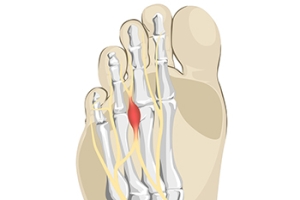

What Causes Morton’s Neuroma?

The foot condition that is known as Morton’s neuroma is painful. It is caused by wearing shoes that do not have enough room in the toe area and it affects the nerve between the third and fourth toes. High heels can fall into this category, and women can develop this condition if high heels are worn often and for long periods of time. Patients may feel this affected nerve can be malignant, however, it is considered to be a benign growth. The pain is often felt in the ball of the foot, and it may be difficult to walk. Temporary relief may be found when wider shoes with lower heels are worn. There may be swelling that accompanies this ailment, and it can be helpful to elevate the feet. In severe cases, some patients may choose surgery that can remove the nerve, and normal activities may be resumed. If you have foot pain from for Morton’s neuroma, it is strongly suggested that you contact a podiatrist who can effectively diagnose and offer the correct treatment methods.

Morton's neuroma is a painful foot condition that commonly affects the areas between the second and third or third and fourth toe, although other areas of the foot are also susceptible. Morton’s neuroma is caused by an inflamed nerve in the foot that is being squeezed and aggravated by surrounding bones.